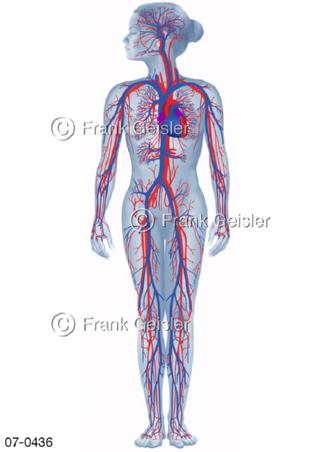

Bilder zu Herz, ein muskuläres Hohlorgan, das den menschlichen Körper durch rhythmische Kontraktionen mit Blut versorgt und dadurch die Durchblutung der Organe sichert, das Kreislaufsystem zeigt den Transport von arteriellem sowie venösem Blut durch das kardiovaskuläre System (Herz-Kreislauf-System), bestehend aus Blutgefäßen, Lymphgefäßen und dem Herz